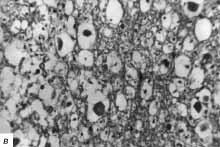

При морфологическом исследовании выявлено:

б - в зоне сдавления массивные кровоизлияния в сером и белом веществе

и многочисленные тромбы в просветах сосудов; окраска гематоксилином и

эозином, ув. 250;

в - некроз ткани спинного мозга на всю его толщу с выраженной лейкоцитарной

реакцией. Некроз нейроцитов с образованием клеток-теней, выраженный перицеллюлярный

отек, реакция глии; ув. 400;

г - рядом с зоной сдавления рисунок строения сохранен, хотя и несколько

стерт, также выражен перицеллюлярный отек и дистрофические изменения нейронов;

ув. 400.

Проведенное морфологическое исследование подтвердило возникновение тяжелых

деструктивных изменений в веществе спинного мозга, развившихся в течение

3-х сут от момента сдавления дужкой шейного позвонка.

Наряду с этим морфологическое исследование выявило распространение ишемических

изменений как в проксимальных отделах спинного мозга, так и дистальных.

Причем, проксимальные отделы страдают в большей степени и на большем протяжении

по сравнению с дистальными. |